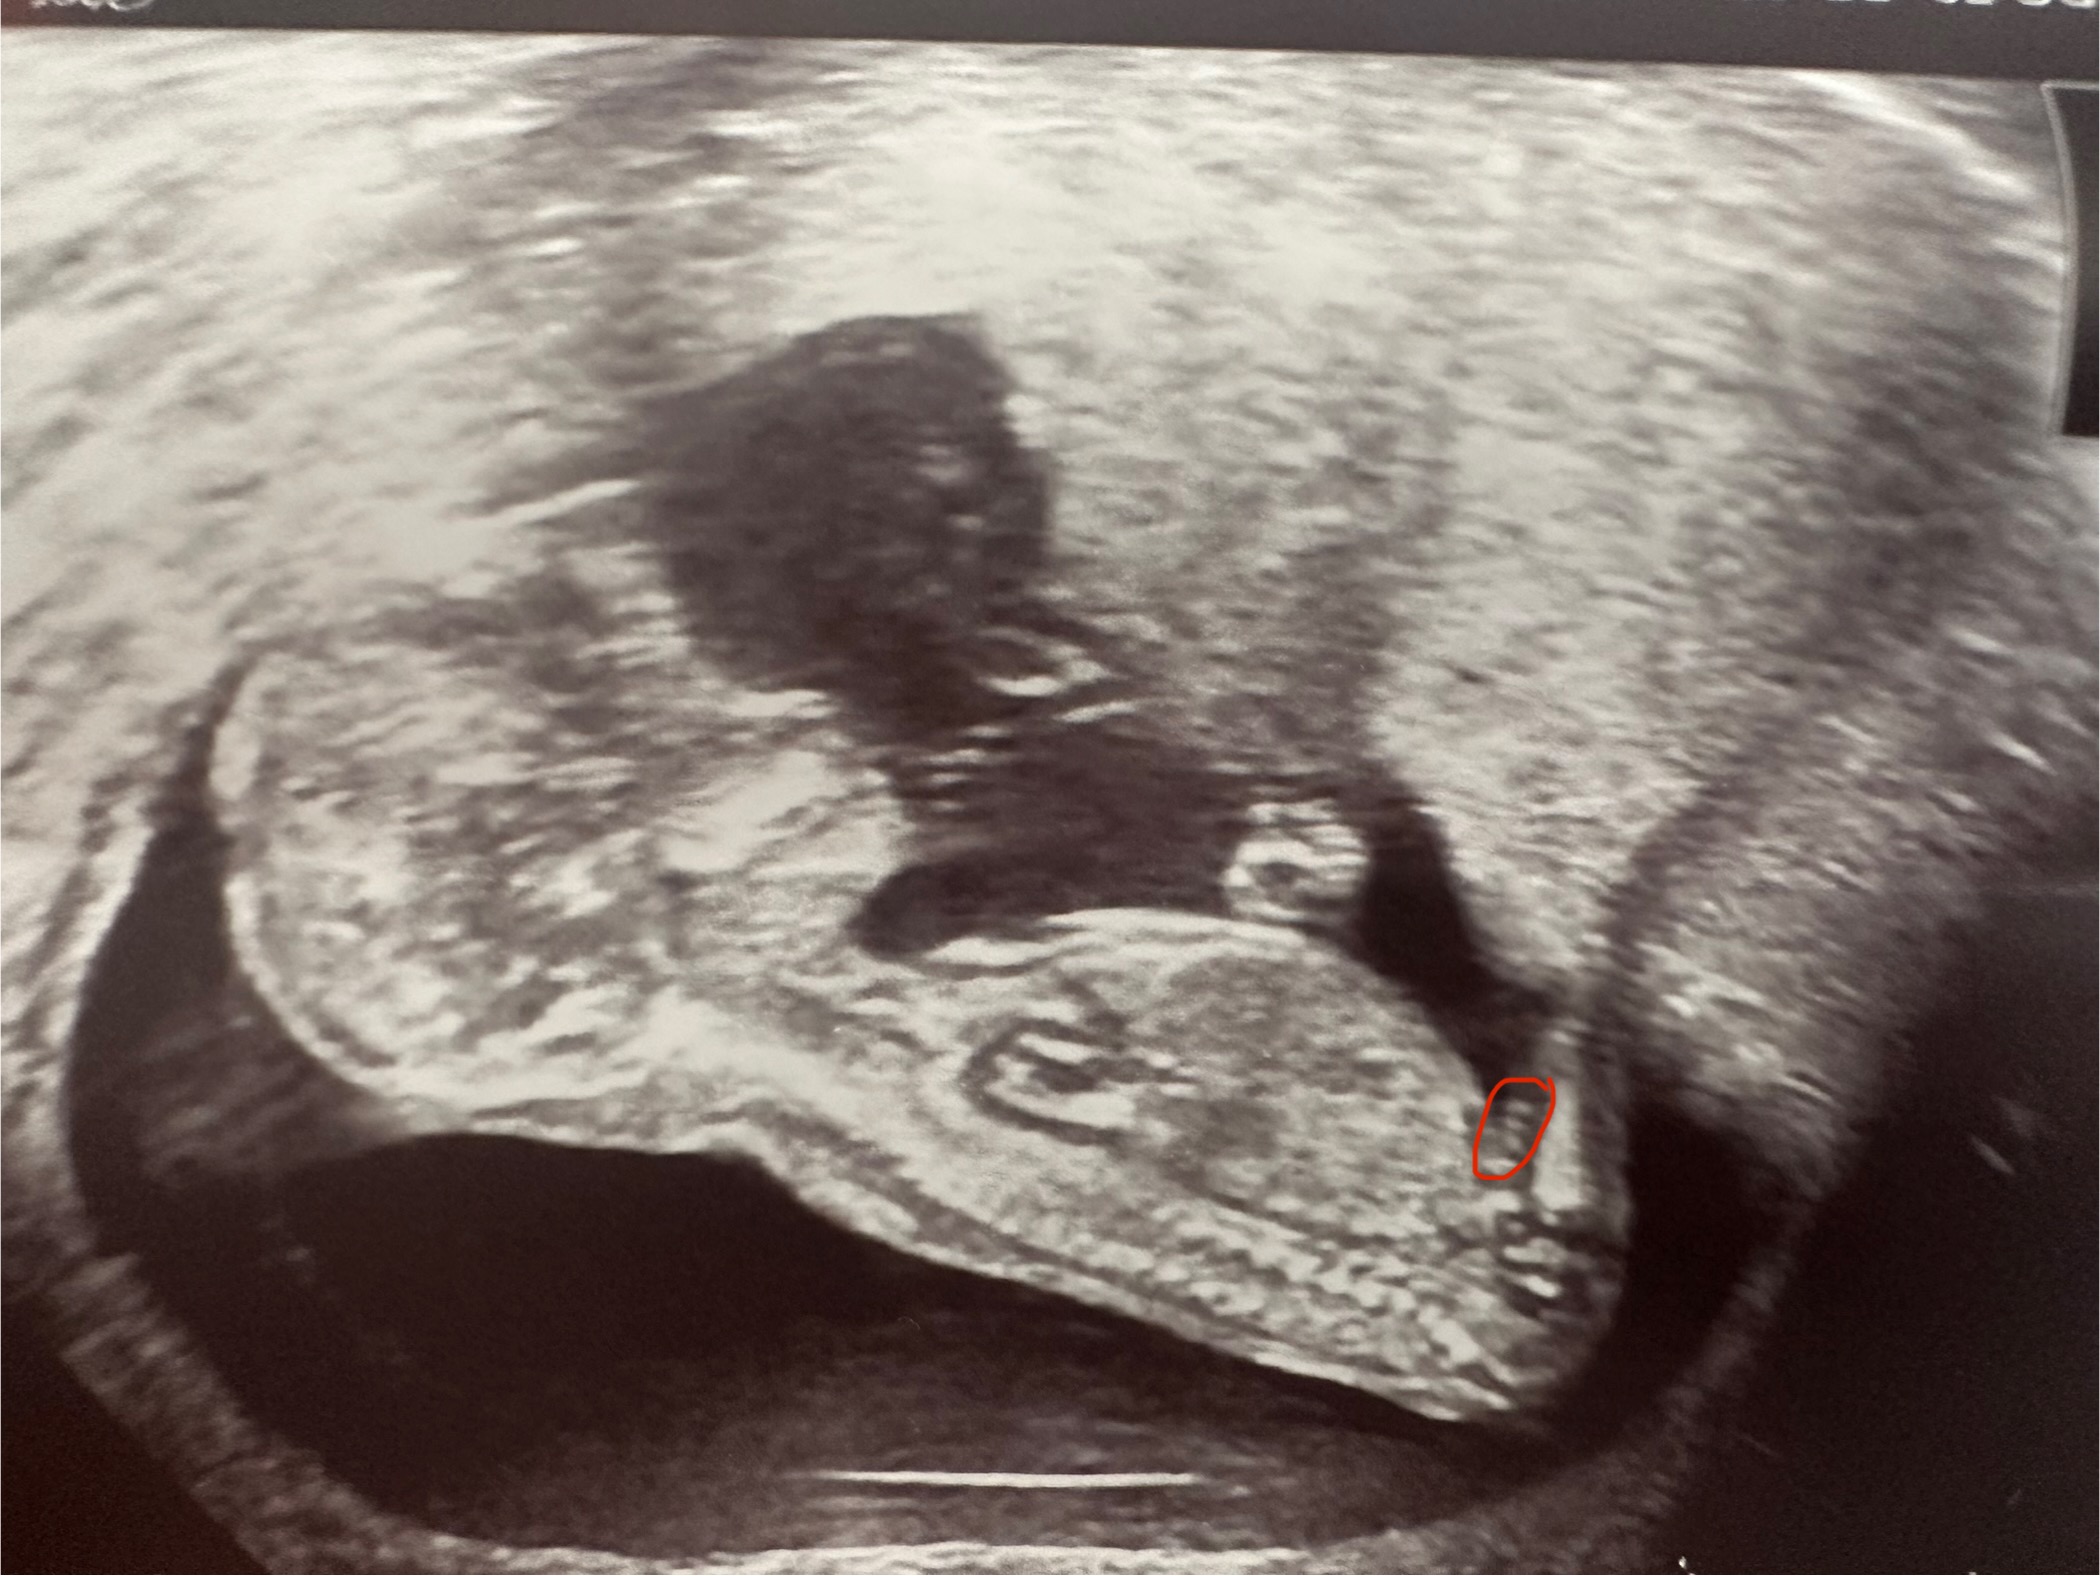

УЗИ в 14 недель

Изображение Мне врач вот эту пипирку показала)

Это нога, смотреть сейчас ни с боку ни снизу не информативно, пограничный срок. В 15-16 недель снизу уже видно

Это бедрышко, там косточка белая. А еще, он пальчик сосет))

Травница, где пальчик-то сосёт? 🙈Одна рука в кулаке сжата, а другая вдоль туловища. Вот пузыри пускает, это чётко видно

🙈 Это бедро.